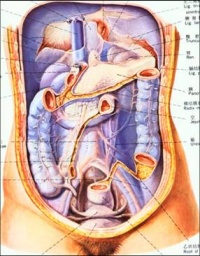

(一)网膜[编辑 | 编辑源代码]

1.小网膜

是连结于肝门与胃小弯、十二指肠上部之间的双层腹膜。形似围在脖下的“餐巾”。右侧部称肝十二指肠韧带,内有胆总管、肝固有动脉、门静脉等结构通过。左侧部称肝胃韧带。

2.大网膜

是连于胃大弯和横结肠之间的四层腹膜。呈“围裙”状悬挂于横结肠和小肠之前。大网膜内含脂肪、血管、淋巴管等,活动度大,有限制炎症蔓延的作用。

3.小网膜

小网膜lesseromentum是联系于肝门与胃小弯、十二指肠上部之间的双层腹膜结构,呈冠状位,含脂肪组织处较厚,其余部分薄而稀疏,呈网眼状。小网膜的左侧部为肝胃韧带hepatogastricligament,系于肝门与胃小弯之间,内含胃左、右动静脉,胃上淋巴结和胃的神经等。右侧部为肝十二指肠韧带hepatoduodenalligament,系于肝门与十二指肠上部之间,其游离右缘肥厚,有胆总管(紧右侧游离缘)、肝固有动脉(位于胆总管的左侧)和门静脉(位于上述二管的后方)走行于其中。

4.大网膜

大网膜greateromentum由自胃大弯双层垂下至盆腔上口高度再向后上反折至横结肠的共四层腹膜构成。成体大网膜四层互相愈合,呈门帘状遮于腹腔下部器官的前方。大网膜疏薄,含有多少不等的脂肪,常呈筛网状。其中前两层自胃大弯下降至横结肠前方并与之愈着,叫做胃结肠韧带gastrocolicligament内有胃网膜血管走行。大网膜组织内含有吞噬细胞,有重要的防御功能。当腹腔器官发生炎症时,大网膜的游离部向病灶处移动,并包裹病灶以限制其蔓延。小儿大网膜较短,故当下腹部器官病变时(如阑尾炎穿孔),由于大网膜不能将其包围局限,常致成弥漫性腹膜炎。

5.胃脾韧带

胃脾韧带gastrolienicligament为连于胃底部和脾门间的双层腹膜结构,与大网膜的左端相续,内含胃短动脉,为脾动脉向胃底的分支。

6.脾肾和脾膈韧带

为系于脾门和左肾前面、膈的双层腹膜结构,其中反折至左肾前面的叫脾肾韧带splenorenalligament,其上端部分附于膈叫脾膈韧带splenophrenicligament 。脾膈韧带上部为自胃贲门和食管腹段系于膈,叫做胃膈韧带gastrophrenicligament。脾肾韧带内有脾血管走行,胰尾亦位于该韧带内。

小网膜、胃后壁和腹后壁腹膜之间的扁窄间隙叫做网膜囊omentalbursa(又称Winslow’s囊)。囊的前壁由上向下依次为小网膜、胃后壁和胃结肠韧带;后壁是覆盖于胰、左肾和左肾上腺前方的腹后壁腹膜,下方还有横结肠及其系膜;上壁为膈下面的腹膜和肝尾叶;下壁为大网膜前两层与后两层的愈合部;左壁为脾、胃脾韧带、脾肾韧带和脾膈韧带;右侧借网膜孔与大腹膜腔相通。

网膜孔omentalforamen(又称Winslow’s孔)上界为肝尾叶,下界为十二指肠的上部起始段(球部),前界为肝十二指肠韧带的游离缘,后界为覆盖下腔静脉的腹后壁腹膜。网膜孔一般仅可通过1-2个手指。